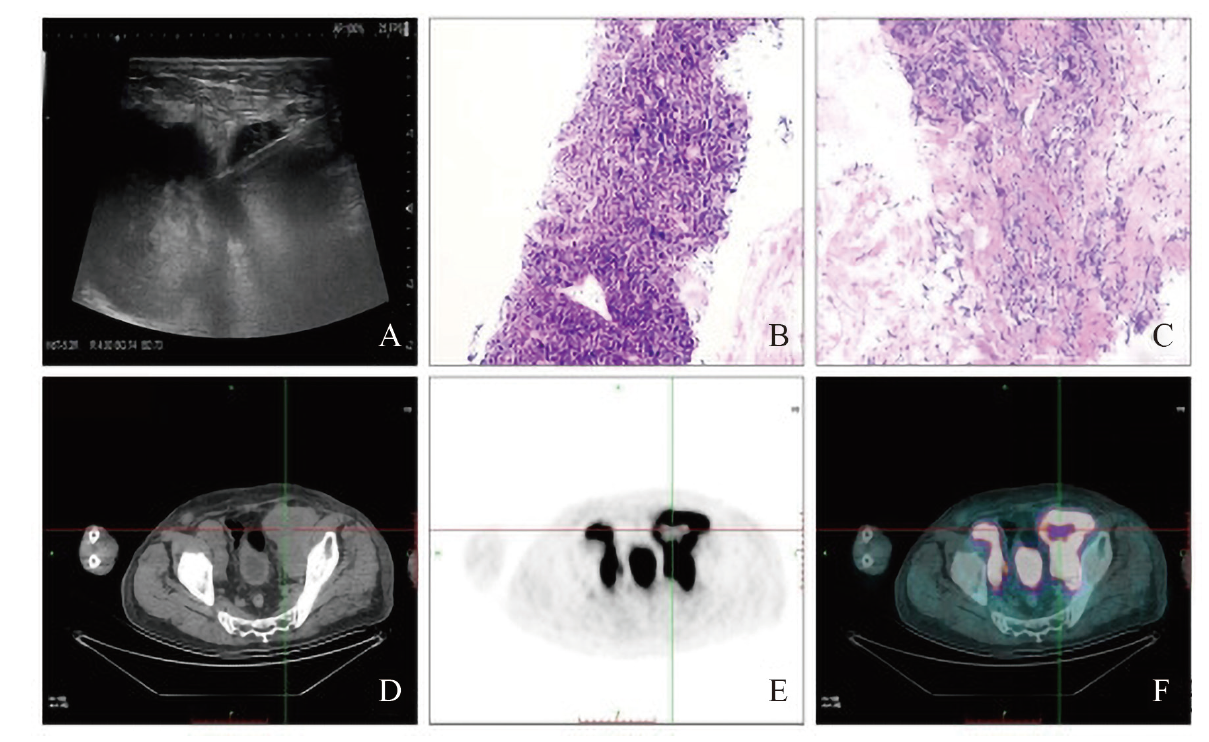

图2 一例浅表淋巴瘤伴坏死患者的超声造影穿刺、病理活检及PET-CT结果

注:A为于超声造影高增强区域穿刺;B、C为HE染色病理活检,检出组织较为完整,组织边缘可见坏死(×10);D~F为PET-CT示左腹股沟淋巴结肿大伴坏死。

左侧腹股沟淋巴结HE染色结合免疫组织化学检查(免疫组化)及原位杂交诊断:弥漫大B细胞淋巴瘤(图2B、C),结合分子检测提示高级别B细胞淋巴瘤伴C-myc、B细胞淋巴瘤2(Bcl-2)、Bcl-6基因重排。患者行淋巴瘤穿刺活检后进一步行PET-CT:口咽右侧壁软组织结节伴氟代脱氧葡萄糖(FDG)代谢异常增高,纵隔内(包括双侧膈肌脚后间隙)、腹膜后腹主动脉旁、双侧髂总血管走行区、盆腔、双侧腹股沟多发淋巴结伴FDG代谢异常增高,左侧腹股沟淋巴结肿大伴坏死(图2D~F)。